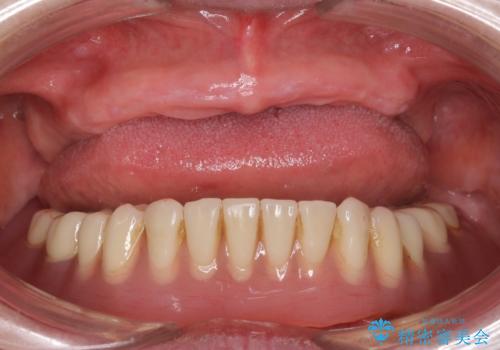

- 上の入れ歯の歯がとれてしまったこと・ゆるくてはずれてしまうことを主訴に来院された患者様です。

精査したところ、長年使用されていた入れ歯は劣化し、人工歯の脱離及び適合不良を認めました。

「ぴったりしていて全然はずれません!」と喜んで下さいました。

古い入れ歯は人工歯がすり減っており左右均等に咬むことができなかったそうですが、新しい入れ歯だと両側でしっかり咬むことができるとご満足頂けました。